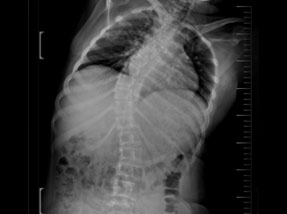

• Pre-Surgery

• Post Surgery

Case 1